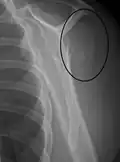

Midshaft humerus fracture with callus formation

Fractures of the humerus shaft are most often uncomplicated, closed fractures that require nothing more than pain medicine and wearing a cast or sling. For midshaft fractures up to 12 weeks may be required for healing.[17]